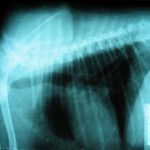

Asimismo, tenemos equipos de diagnóstico médico-veterinario para que usted y su mascota puedan beneficiarse sin salir de casa.